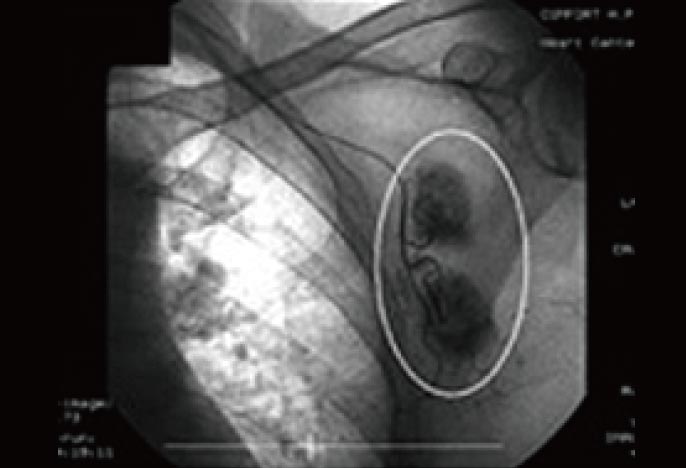

治療前のCT検査

治療前に、血管カテーテルから造影剤を入れて、転移したがんそのものを調査した時の両像です。

わきの下の太い血管周囲に、もやもやとしたがんの新生血管が密に認められます(円の中の黒々とした部分)。当然ここまで進んでしまうと抗がん剤や放射線治療など、いわゆる保険治療で実施される標準治療自体、根治の見込みはありません。まさに“治療の手立てなし”という状況です。推定された予後寿命は、およそ3ヶ月から1年程度。保険治療、あるいは細かい調整の一切不可能な民間療法だけに頼っていたのでは、まもなくホスピス・緩和ケア病棟への入院も予想されました。